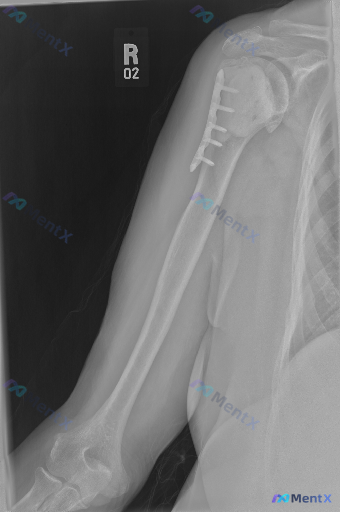

整理到一张右肩部及上臂正位X光片的资料,来自一位肱骨近端骨折术后复查的患者。 影像上能看到:右肱骨近端外侧有金属接骨板和数枚螺钉固定,螺钉位置在骨骼内,未见明显金属断裂或松动;骨折断端(推测外科颈附近)有连续骨痂形成,骨小梁有跨越迹象,皮质连续性良好,未见新发骨折线;盂肱关节、肩锁关节对位尚可,关节...